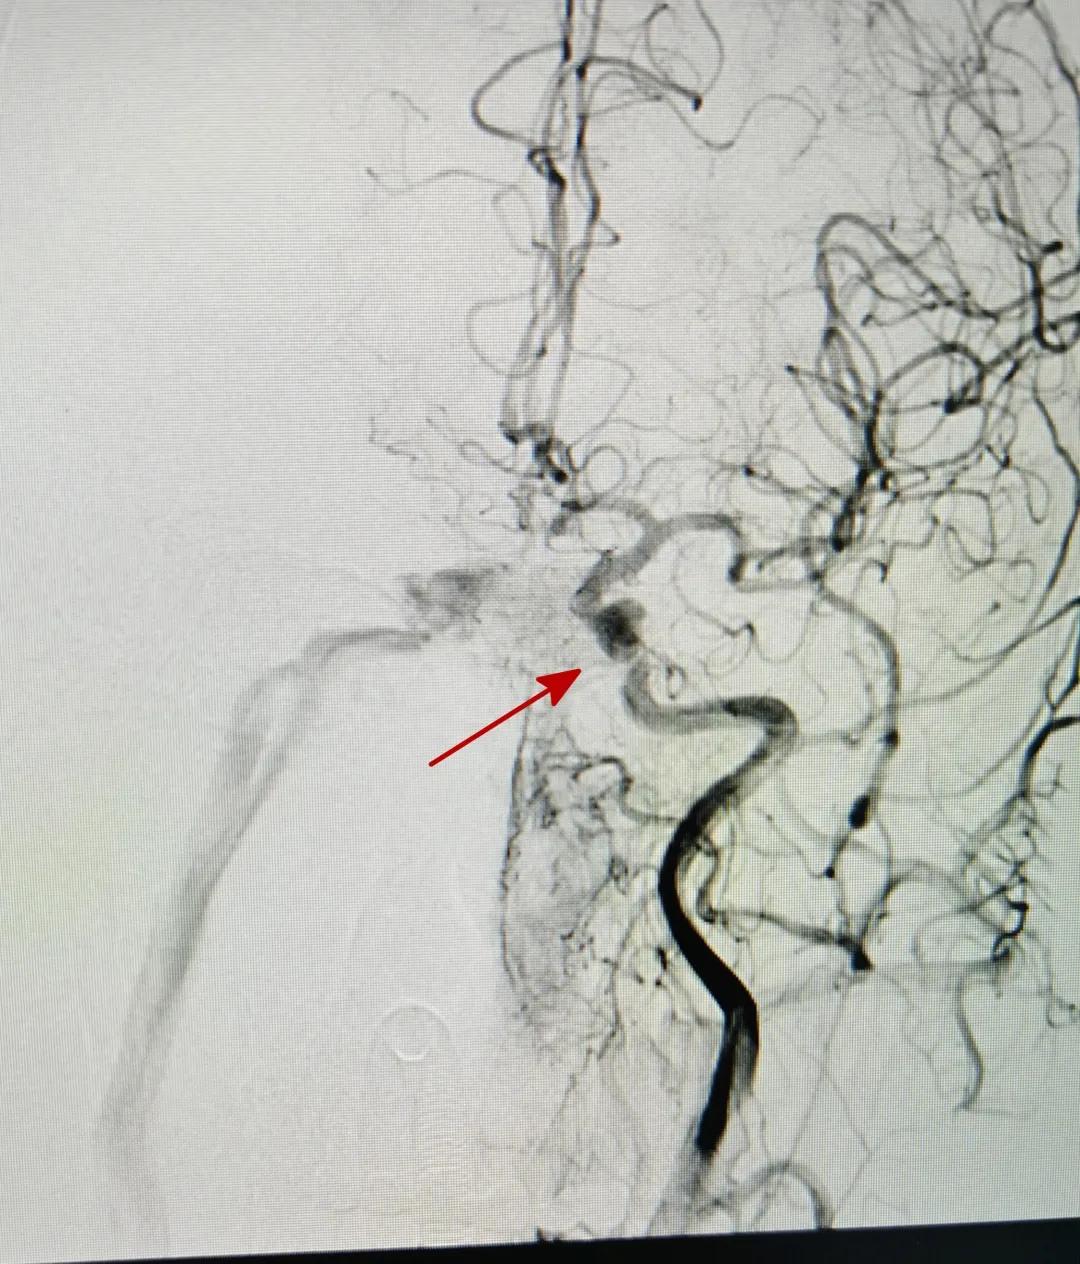

患者术前脑血管造影

要治疗这种病,就需要把和海绵窦连通的异常血管(医学上叫“瘘口”)封堵住。以往常规的治疗方法是经动脉介入栓塞术,其原理是挨个寻找瘘口,并一一将其堵死。但是瘘口异常连通的血管有很多,并且很细,这给手术增加了很多难度,而且动脉血可能再次跑到海绵窦的静脉系统。而经静脉栓塞介入栓塞术的原理则是将海绵窦填塞,这样既堵住了回流静脉,又将动脉血拦截在海绵窦的静脉系统外,大大提高了成功率,减少了复发率。

针对患者病情,神经外科医生胡克琦和周达全带领介入团队进行了详细的研究,最终决定为患者行海绵窦区硬脑膜动静脉瘘经静脉岩下窦入路介入栓塞术。